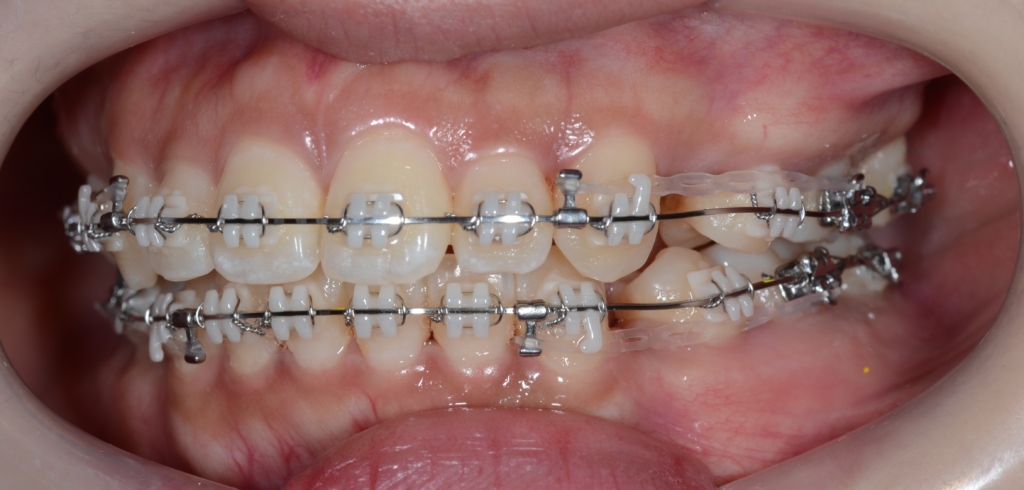

【治療開始】

順調にステップが進み、前歯を最大限に引っ込めるステップに入りました。

【上の歯列の更なる後方への移動を図る】

隙間分はしっかり引っ込めたのですが、元の噛み合わせが上顎前突傾向でしたので、出っ歯が残ってしまいました。 そこで、より引っ込んだ下の歯列に上の歯列を引っ込めて合わせるという次のステップに進めることにしました。

あらためて、上顎にアンカースクリューを植立しました。

アンカースクリューを用いて矯正力を加えることで、上顎歯列全体を後方へ移動させて、口元の見た目の更なる改善を図ります。

同じことをしている方の写真をイメージ写真としてあげています。